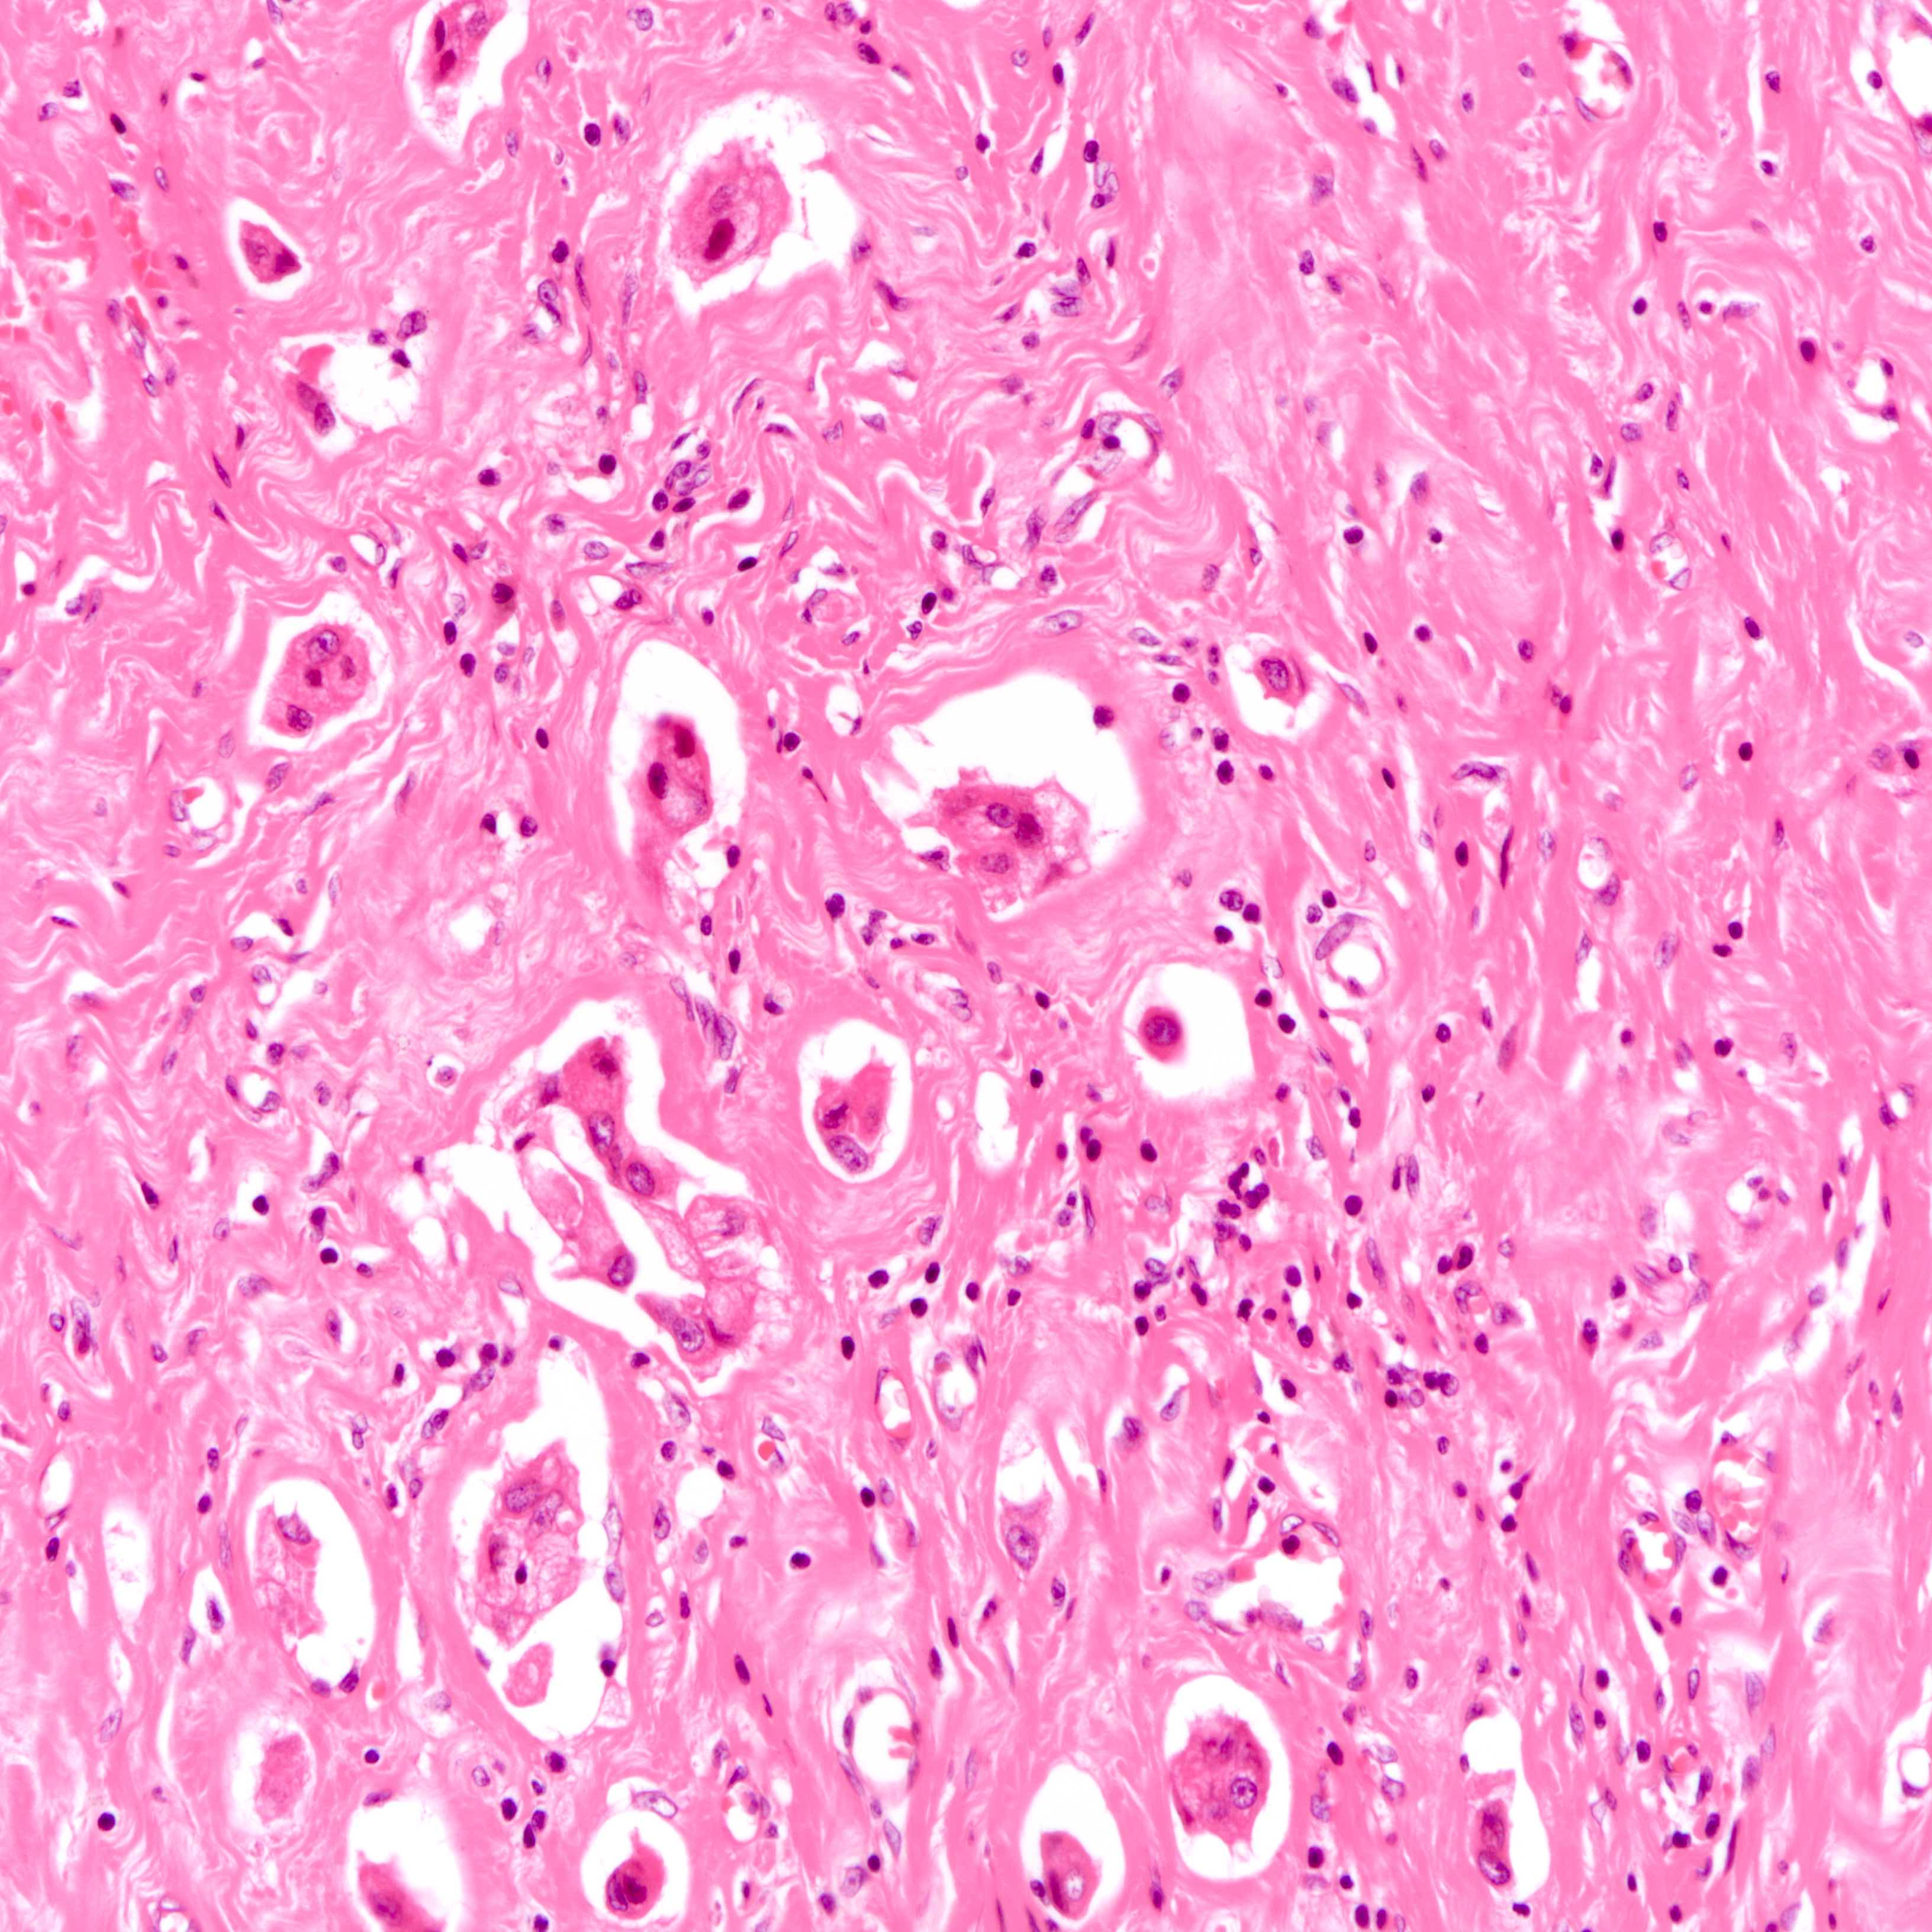

- Histologic evidence of tumor response includes fibrosis, hyalinization, lymphohistiocytic infiltration, hemosiderin laden macrophages, giant cell formation and vascular proliferation

- These histologic features are indicative of the tumor bed

- Patterns observed in partial response includes concentric tumor shrinkage, reduction in tumor cellularity and scattered multifocal tumor deposits (Mod Pathol 2015;28:1185)

- Tumor cells show degenerative changes including nuclear and cytoplasmic vacuolation, karyorrhexis, karyolysis and pyknosis (Int J Appl Basic Med Res 2012;2:111)

- Lymph node

- Possible scenarios include

- Presence of tumor cells, with no evidence of histologic treatment response

- Presence of tumor cells, histologic evidence of treatment response seen

- Absence of tumor cells, histological evidence of treatment response seen

- Absence of tumor cells and histologic evidence of treatment (true negative nodes)

- Histological evidence of tumor response in the lymph node includes fibrosis, mucin pools, histiocytic infiltrates and lymphoid depletion

- Presence of tumor response indicates possible previous nodal involvement and is associated with prognosis intermediate between node negative and node positive patients (Ann Surg Oncol 2003;10:734)

Microscopic (histologic) images

Contributed by Joshua J.X. Li, M.B.Ch.B., Gary M. Tse, M.B.B.S. and Emily S. Reisenbichler, M.D.